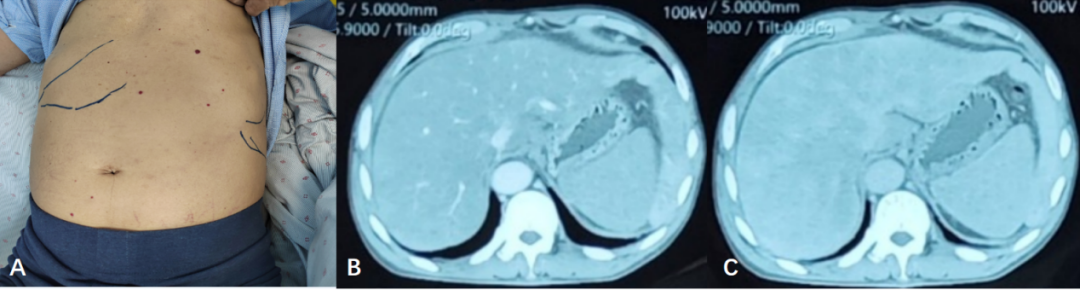

查体:体型消瘦,身高170cm,体重45kg,BMI 15.5kg/m2,皮肤黏膜轻度黄染,腹部膨隆,无压痛及反跳痛,肝脏右肋下5cm可触及,质中,脾脏左肋下可触及,质中(肝脾下界见图1A),移动性浊音阴性,双下肢无浮肿。

图1.A腹部体征,肝脾下界;B、C腹部增强CT门静脉期、平衡期

影像检查提示肝脏不均匀强化且肝内静脉未显影时,并非一定指向肝脏血管性疾病。这一表现也可能由肝脏不均匀性坏死,或异常物质沉积引发的肝脏灌注失衡所致,临床需注意鉴别肝窦阻塞综合征、布加综合征、急性重症肝炎不均匀肝损害等。其中,肝淀粉样变性的典型影像特征为肝脏增大,伴肝内弥漫性低密度影,增强扫描时强化效应不明显,且肝内血管无移位,此特征可作为重要鉴别依据。